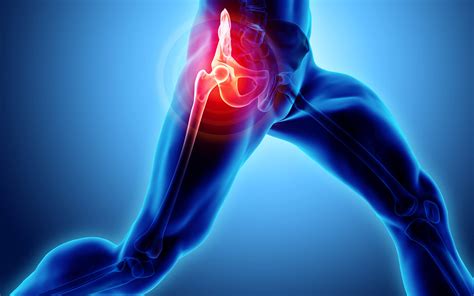

Avascular necrosis (AVN), also known as osteonecrosis, is a complex and often debilitating condition that occurs when the blood supply to a bone is disrupted. Without a steady supply of oxygen-rich blood, bone tissue begins to die, eventually leading to the collapse of the bone structure. Because early intervention is critical to preserving joint function and preventing long-term disability, recognizing Avascular Necrosis Symptoms is the most important step in the treatment process. This condition most commonly affects the hip, but it can also manifest in the knee, shoulder, ankle, and wrist.

As the bone begins to collapse, the pain typically becomes much more severe and constant. Activities that were once effortless, such as walking or standing for long periods, may become impossible. Patients often notice a distinct "limp" developing, which is the body’s natural reaction to avoiding weight on the compromised joint.

| Hip | Groin or buttock pain | Difficulty walking or standing |